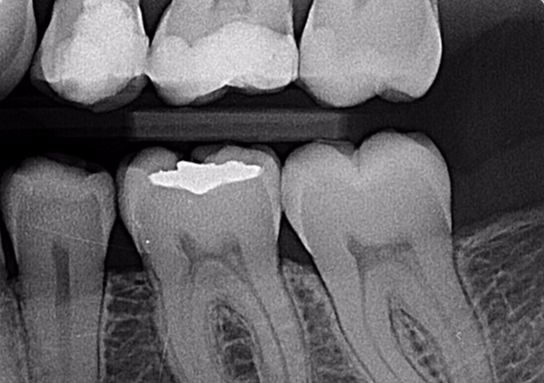

Radiografias Periapicais Digitais

Tem como objetivo visualizar os ápices das raízes dos dentes e das estruturas que os rodeiam. É utilizada para pesquisa e lesões periapicais e periodontais, fraturas, anomalias, reabsorções e outras lesões que atingem os dentes.

O Levantamento Periapical é o exame mais completo dentro do grupo das radiografias periapicais, sendo

composto de 14 radiografias.